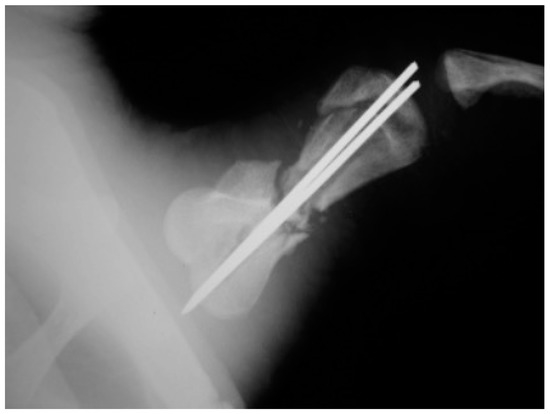

A juvenile sea turtle was presented to the Sea Turtle Clinic (STC) of Veterinary Medicine Department of the University of Bari with an entanglement lesion affecting the right front flipper. On admission, the sea turtle was measured and underwent a complete physical examination; curved carapace length (CCL) from notch to tip ranged 41 cm, curved carapace width (CCW) was 37 cm, and the weight was 18 Kg. The turtle appeared responsive but weak and dehydrated. Clinical evaluation of the musculoskeletal system performed out of the water showed swelling of the right front flipper and evidence of pain on deep palpation of the respective brachial muscle. A reduction in the right front flipper’s range of motion was observed when the turtle was examined in the water. Radiographic assessment, in dorso-ventral (D-V) and Caudo-Cranial (C-C) projections, indicated detachment of the distal epiphysis of the humerus, compatible with a type II Salter-Harris fracture, together with a transverse diaphyseal fracture (Figure 1). The turtle underwent general anesthesia, and the craniodorsal access to the humeral diaphysis was performed. The epiphyseal fracture was reduced by closed surgery and fixed using two crossed 2.5 mm Kirschner pins, introduced backward from the distal stump and brought out through the hyperflexed humerus-radio-ulnar joint. The same pins used to fix the epiphyseal fracture were inserted into the proximal stump to fix the diaphyseal fracture. After checking the stability of the fractures reductions, the surgically sectioned soft tissues were reconstructed, and post-operative radiographs were performed. Follow-up was performed after the surgery at 2, 4, 12, 16, and 24 months, when the turtle was released at sea. Three months after its release at sea, the turtle was caught dead in a fishing net at a depth of 40 m. To determine the evolution of bone repair from turtle release to death, the right humerus was removed for histological and histomorphometry analyses. Immediately after explant, the humerus was fixed in 4% buffered paraformaldehyde, dehydrated in ethanol, and embedded in methylmetacrylate. Serial cross sections, 750 µm thick, were cut at both the diaphyseal and epiphyseal fracture gaps using a circular diamond-bladed saw (Gillings Hamco) and were ground to a thickness of 100 µm. Sections were placed on a specimen holder and microradiographed using a microradiograph (Constant 1-K, Ital Structures, Italy) at a prefixed distance from the X- ray generator of 9.5 cm. X-ray exposure was set up at 8 kV and 14 mA. Contact microradiographs were obtained on Kodak high-resolution film (SO 343, Eastman Kodak Co., Rochester, NY, USA), developed with Kodak HC-110, fixed in Kodak UNIFIX, washed in distilled water and then airdried at room temperature. Sections were subsequently stained with 1% toluidine blue (pH 3.7) for mineralized tissue. Four separate levels were selected, three belonging to the mid-diaphyseal fracture gap, and one level to the epiphyseal fracture gap: the first and the fourth levels corresponded to the proximal and distal part of the callus, respectively, and the second and third levels to the center of the fracture (Figure 2). As a control, the left humerus, which had never been fractured, was processed with the same procedure. On the stained sections, using a Nikon DS-5 camera connected to a stereomicroscope (SMZ800, Nikon Europe B.V., Amstelveen, The Netherlands) and a DS camera control unit, the callus extension was measured and the amount of new laid down bone, cartilage, and fibrous tissue, expressed as percentage ratio of the entire section, were evaluated. Histomorphometry was performed using Nis-Elements BR analysis software (Nikon Europe B.V.).

Figure 2. X-ray image of the humerus showing the levels from which the histological and morphometric findings and the microradiographs. Numbers 1 to 4 correspond to the first, second, third and fourth diaphyseal level, respectively. Number 5 corresponds to the distal epiphysis level.